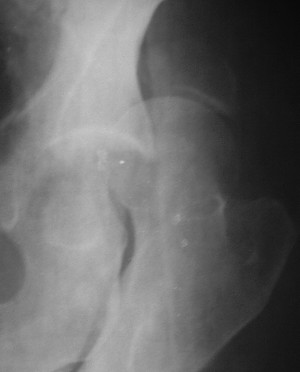

Считаю, что в представленном Вами случае целесообразно подумать о первичном протезировании. Привожу пример более легкого повреждения, где потерял время надеясь спасти сустав.

19/05/03

Больной 18 мая 2003 года в автоаварии получил перелом левой вертлужной впадины, вывих бедра. Госпитализирован в один из стационаров области.Вывих вправлен. В последствии бедро вывихивалось еще дважды. На консультацию был представлен снимок от 19.05.03г., больной переведен к нам 3.06.03г. Снимок при поступлении - перелом впадины, задне-верхний вывих бедра. 05.06.2003 г. выполнено открытое вправление вывиха левого бедра и остеосинтез стенки вертлужной впадины двумя винтами. Послеоперационный период без осложнений. Объем движений в левом тазобедренном суставе восстановился полностью. Выписан на амбулаторное лечение в удовлетворительном состоянии с рекомендациями 3 месяца ходить на костылях без нагрузки на оперированную конечность. На контрольных рентгенограммах левого тазобедренного сустава 13.10.2003 г. - признаки консолидации перелома; плотность, форма головки и состояние суставных поверхностей удовлетворительные. Разрешена дозированная осевая нагрузка, на конечность с использованием дополнительной опоры. 19.12.2003 г. больной обратился с жалобами на боли в левом тазобедренном суставе. На рентгенограммах левого тазобедренного сустава 19.12.2003 г., 20.02.04г. - асептичекий некроз головки бедра. 5.04.04г. - эндопротез. Сейчас ходит без трости, не хромает. Особенность эндопротезирования - при удалении винтов прослежена линия перелома заднего края впадины и предложено установить чашку несколько меньшего диаметра, чтобы она была покрыта несломанной частью.